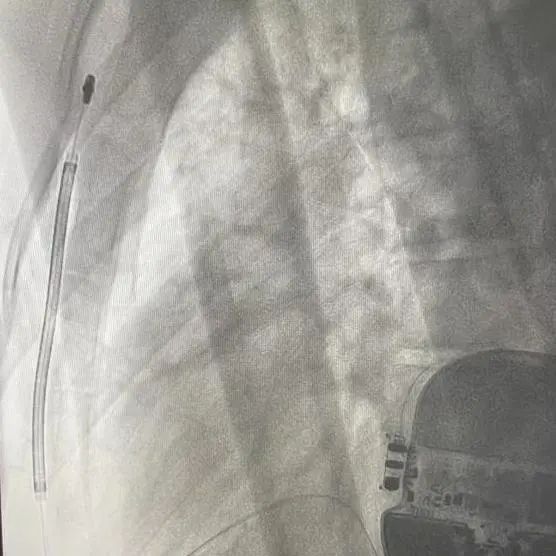

手术在全麻醉下进行。常规消毒、铺巾,取左腋中线平等第5-6肋为预定点,切开一约7cm切口,逐层将皮下组织分离直至肌层,在前锯肌与背阔肌之间寻找到深筋膜层,以确保囊袋在患者的脂肪层下并且足够容纳装置。

再次于胸骨柄右缘1cm为预定点,切开一长约4cm切口,逐层分离至深筋膜层,预埋两根缝合线用导引针,于切口间建立隧道,利用隧道针将电极沿皮下置入囊袋。再以切口位置建立隧道,同样以隧道针将导线头端沿深筋膜层,送至胸骨柄上缘(距切口14cm处,于切口处固定电极导线,囊袋处连接脉冲发生器(S-ICD A209),固定脉冲发生器于深筋膜层。

排除空气后关闭深筋膜层,进行DFT测试。两位患者均采用50HZ,200MA交流电方式进行诱颤,SICD均正确识别且65J除颤一次成功,除颤阻抗分别为85欧姆和59欧姆。缝合皮肤,术区纱布覆盖,包扎,弹力绷带加压包扎止血。手术圆满成功。第一台手术耗时2小时,第二台手术仅耗时1个半小时。

患者一:

患者二:

根据Praetorian评分,在术后影响下评估。两位患者评分均为30分。

(Praetorian评分越低,术后除颤风险越低,30分为最低分数)